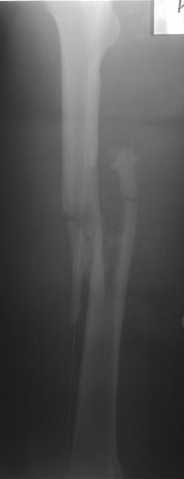

В нашем случае 21 летний боец уличного фронта, фиксацию провели на следующий день, зафиксирован интрамедуллярным штифтом. Не стали делать первичную хирургическую обработку точечной раны, зафиксирован как есть. Клинические снимки:

Конечно, наш случай не эталон, возможно, на месте вам виднее, может быть, нет необходимости ориентироваться на зарубежные ссылки, если получается лечить аппаратом Илизарова на месте, почему нет? Необходимо посмотреть собственный арсенал, чем фиксировать, и какая теория, иначе любой отличный метод можно превратить в источник остеомиелита.